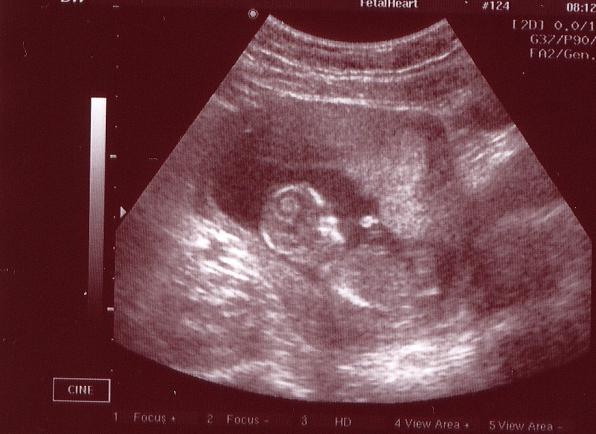

Íme egy mai kép (12+5)!

Mindene megvan! Orrcsont ok, nyakiredő ok! Jelenleg rendellenesség nem látható! Fejlődik ezerrel! :lol: